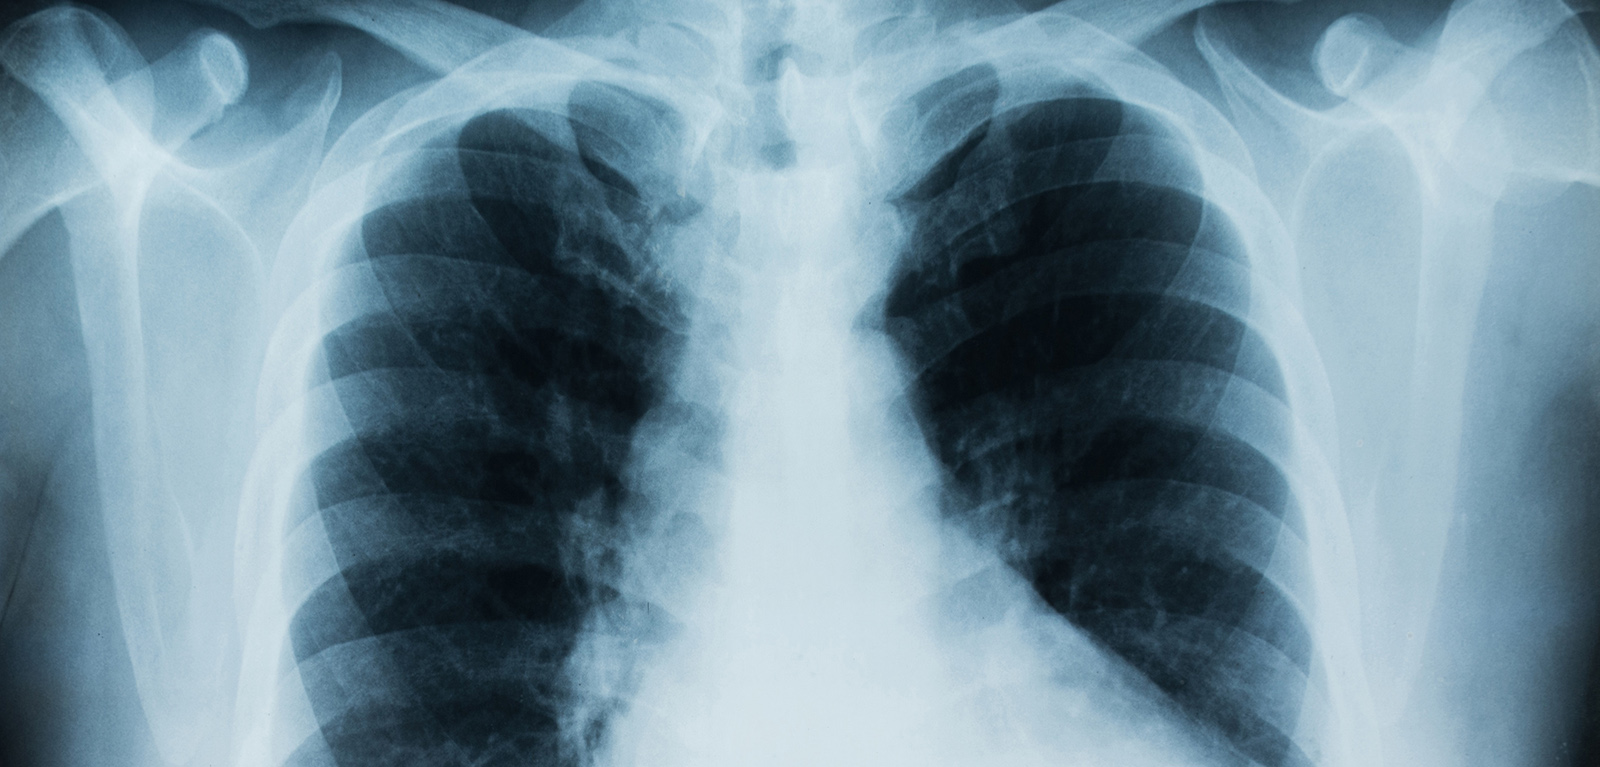

Cystic Fibrosis is a life-limiting genetic disease that affects many organs in the body, particularly the lungs. People with CF (pwCF) have a range of symptoms including, breathlessness, sputum production and the inability to effectively digest food. Additional complications include liver failure, diabetes, bone disease and infertility. Until recently, treatments have been focused on symptom control, however, during the last decade, the work of the Queen’s University Belfast CF Research Team has been at the forefront of major advancements in drugs targeting the underlying genetic deficit.

Delivery of the trials in Belfast has brought huge benefits to the local population of pwCF and provided early access to treatments not yet available as part of standard care. Trial results showed improvements in key outcomes, for example, lung function, sweat chloride (an in-vivo marker of CFTR function), quality of life and bodyweight. Results from a Trikafta/Kaftrio trial also showed a reduction in pulmonary exacerbations of 63%.